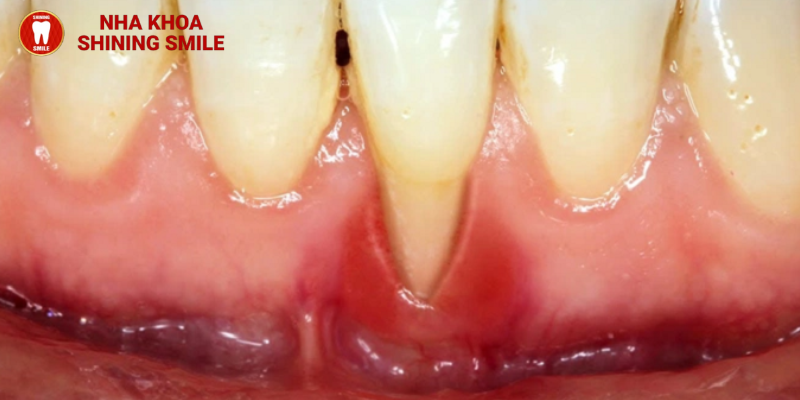

Sau vẻ đẹp thẩm mỹ mà phương pháp này mang lại thì tác hại của niềng răng là gì? Bài viết dưới đây của SHINING SMILE sẽ đi sâu vào những tác động của quá trình niềng răng để bạn tham khảo trước khi đưa ra quyết định “nâng cấp” hàm răng của mình.